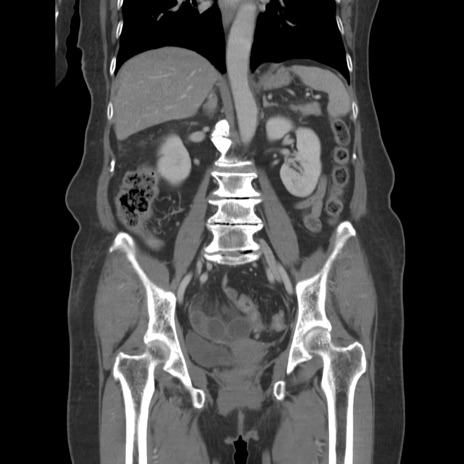

症例19(冠状断像)

【症例】80歳代女性

【主訴】下腹部痛

【現病歴】約8時間前より下腹部痛の出現あり、救急外来受診。

【既往歴】両側付属器切除

【身体所見】意識清明、下腹部正中に手術痕あり、その部位に一致して圧痛と反跳痛あり。腸蠕動音は亢進。

【データ】WBC 9300、CRP 0.15